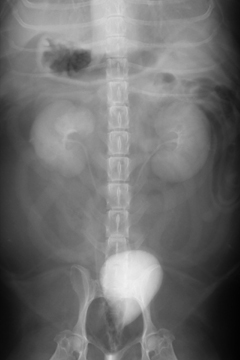

An IVP (intravenous pyelogram, a.k.a. excretory urogram) is performed by infusing contrast medium through the cephalic or jugular vein. Excretory urography can be used to define anatomic structures and relative kidney function.